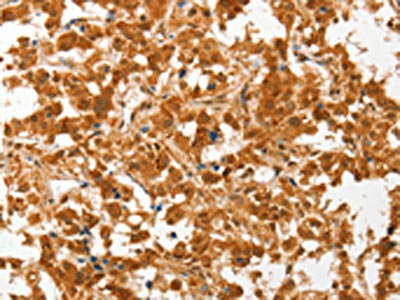

The image on the left is immunohistochemistry of paraffin-embedded Human thyroid cancer tissue using CSB-PA223164(COL4A3BP Antibody) at dilution 1/50, on the right is treated with fusion protein. (Original magnification: ×200)

The image on the left is immunohistochemistry of paraffin-embedded Human gastric cancer tissue using CSB-PA223164(COL4A3BP Antibody) at dilution 1/50, on the right is treated with fusion protein. (Original magnification: ×200)